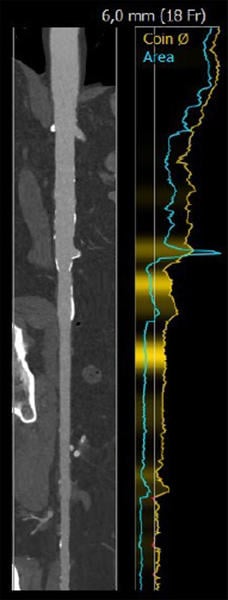

Fallplanung: CT

Anulus: 29,6 cm

LVOT: 32,2 cm

Mäßige Ca2+, Trikuspid